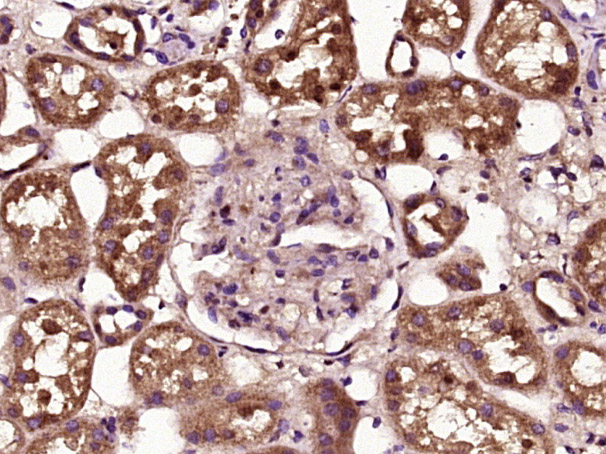

| 英文名称 | phospho-BAD (Ser99) Rabbit pAb |

| 中文名称 | 磷酸化相关死亡促进因子抗体 |

| 产品应用 | IHC-P=1:100-500, IHC-F=1:100-500, IF=1:100-500 Not yet tested in other applications. |

| {IHC-P} | {1:100-500} |